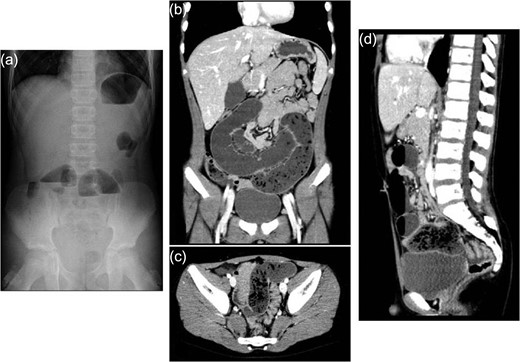

An 11-year-old boy presented with abdominal pain and emesis. Abdominal X-ray revealed multiple air-fluid levels within the small bowel (Fig. 1a). He was transferred to our hospital with the presumed diagnosis of ileus. The patient was afebrile and physical examination showed lower abdominal tenderness without peritoneal signs. Laboratory tests revealed a white blood cell (WBC) count of 13000 /μL and C-reactive protein (CRP) level of 0.07 mg/dL. Enhanced computed tomography (CT) revealed dilated and non-dilated segments of bowel showing the small bowel feces sign, which is defined by the presence of feces-like material mixed with gas bubbles in the lumen of dilated loops of small bowel proximal to the site of an obstruction (Fig. 1b–d). He underwent laparoscopic-assisted surgery. An Alexis XS wound retractor (Applied Medical Resources Corporation, Rancho Santa Margarita, CA) was inserted through a 2.0-cm vertical transumbilical incision, and a silicone cap (Free Access; TOP Corporation, Tokyo, Japan) was mounted for use as a multichannel port. Two 5-mm ports, for the flexible laparoscope and for grasping forceps, were inserted through this multichannel port. Intraoperative findings revealed dilated and non-dilated segment of bowel in the ileum (Fig. 2a). In the terminal part of dilated bowel, a Meckel’s diverticulum associated with a mesodiverticular band was noted (Fig. 2b). Upon closer inspection, the Meckel’s diverticulum was tethered to the small bowel mesentery by a mesodiverticular band and the small bowel proximal to the mesodiverticular band was dilated. We conjectured that the dilated Meckel’s diverticulum filled with intestinal contents and compressed the intestine because of the tethering to the small bowel mesentery, with resultant small bowel obstruction and dilatation of the small bowel proximal to the mesodiverticular band (Fig. 2c–e). To decompress the bowel, intestinal contents were expressed after excision of the Meckel’s diverticulum (Fig. 2f). Intestinal contents consisted of foreign objects and food debris (Fig. 2g). The Meckel’s diverticulum was resected using the Endo-GIA stapler. Upon further questioning postoperatively, it became known that the patient ate two citrus fruits (Citrus maxima) with locular membranes several days prior to his presentation (Fig. 2h). The foreign objects retrieved from the intestinal contents were found to be the locular membranes of said citrus fruit. He was discharged uneventfully on postoperative Day 13.

Abdominal X-ray and enhanced computed tomography. (a) Abdominal X-ray on admission showing multiple air-fluid levels. (b–d) Enhanced computed tomography showing small bowel feces sign, which is defined as the presence of feces-like material in the lumen of dilated loops of small bowel proximal to the site of obstruction.